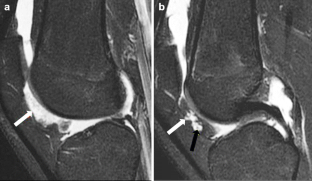

Synovium is the thin membranous lining of a joint. It produces synovial fluid, which lubricates and nourishes the cartilage and bone in the joint capsule. Synovial diseases in children can be classified as normal structures as potential sources of pathology (synovial folds: plicae, infrapatellar fat pad clefts), noninfectious synovial proliferation (juvenile idiopathic arthritis, hemophilic arthropathy, lipoma arborescens, synovial osteochondromatosis, pigmented villonodular synovitis, reactive synovitis), infectious synovial proliferation (pyogenic arthritis, tuberculous arthritis), deposition disease (gouty arthropathy), vascular malformation, malignancy (metastasis) and intra-/periarticular cysts and cyst-like structures. Other intra-articular neoplasms, such as intra-articular synovial sarcoma, can mimic synovial disease in children.